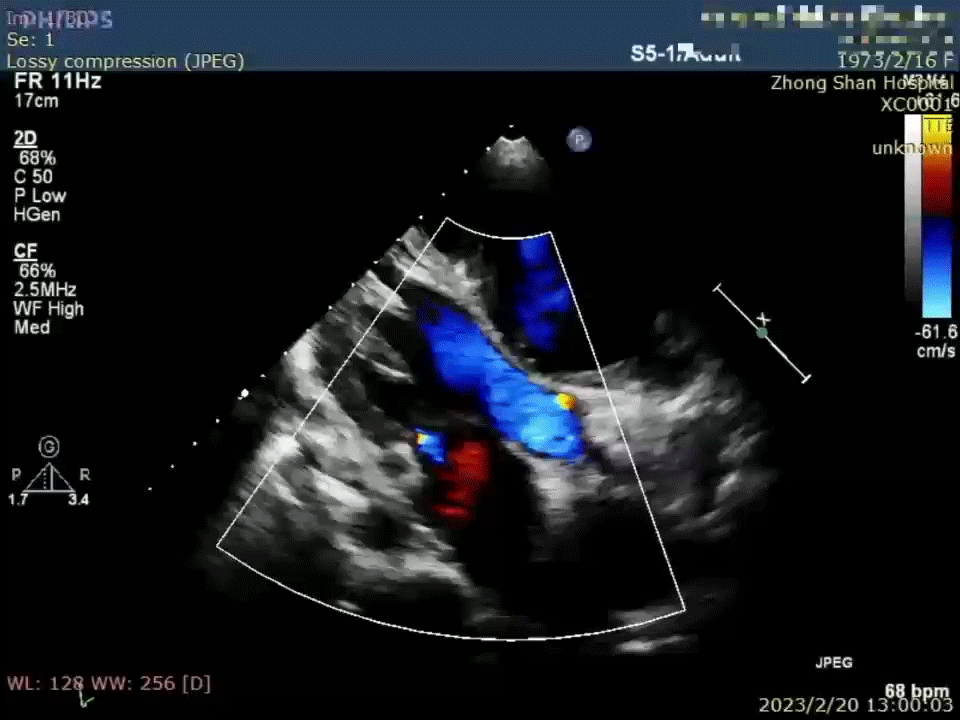

术前:受试者病情较重,6分钟步行距离未能有效测出,NT-proBNP 5229 pg/ml,NYHA III级;术中使用器械规格为7mm,术后即刻超声提示分流器植入位置合适,右向左分流稳定;出院前相关检查结果提示患者肺高压临床症状得到改善。

术后12个月超声

随访检查6分钟步行距离为314m,提示受试者运动能力较术前明显提升, KCCQ评分提示受试者生活质量也明显改善,同时 NT-proBNP 2730 pg/ml, NYHA II级、肺动脉平均压及心脏结构参数等结果提示受试者病情无进展,肾小球滤过率有所增加;另外心超结果提示受试者分流器位置、形态、右向左分流量与术后即刻对比无明显变化。结合术后3个月、6个月的相关检查的临床随访数据综合分析发现该受试者术后临床症状不断改善,运动能力和生活质量也不断提高。